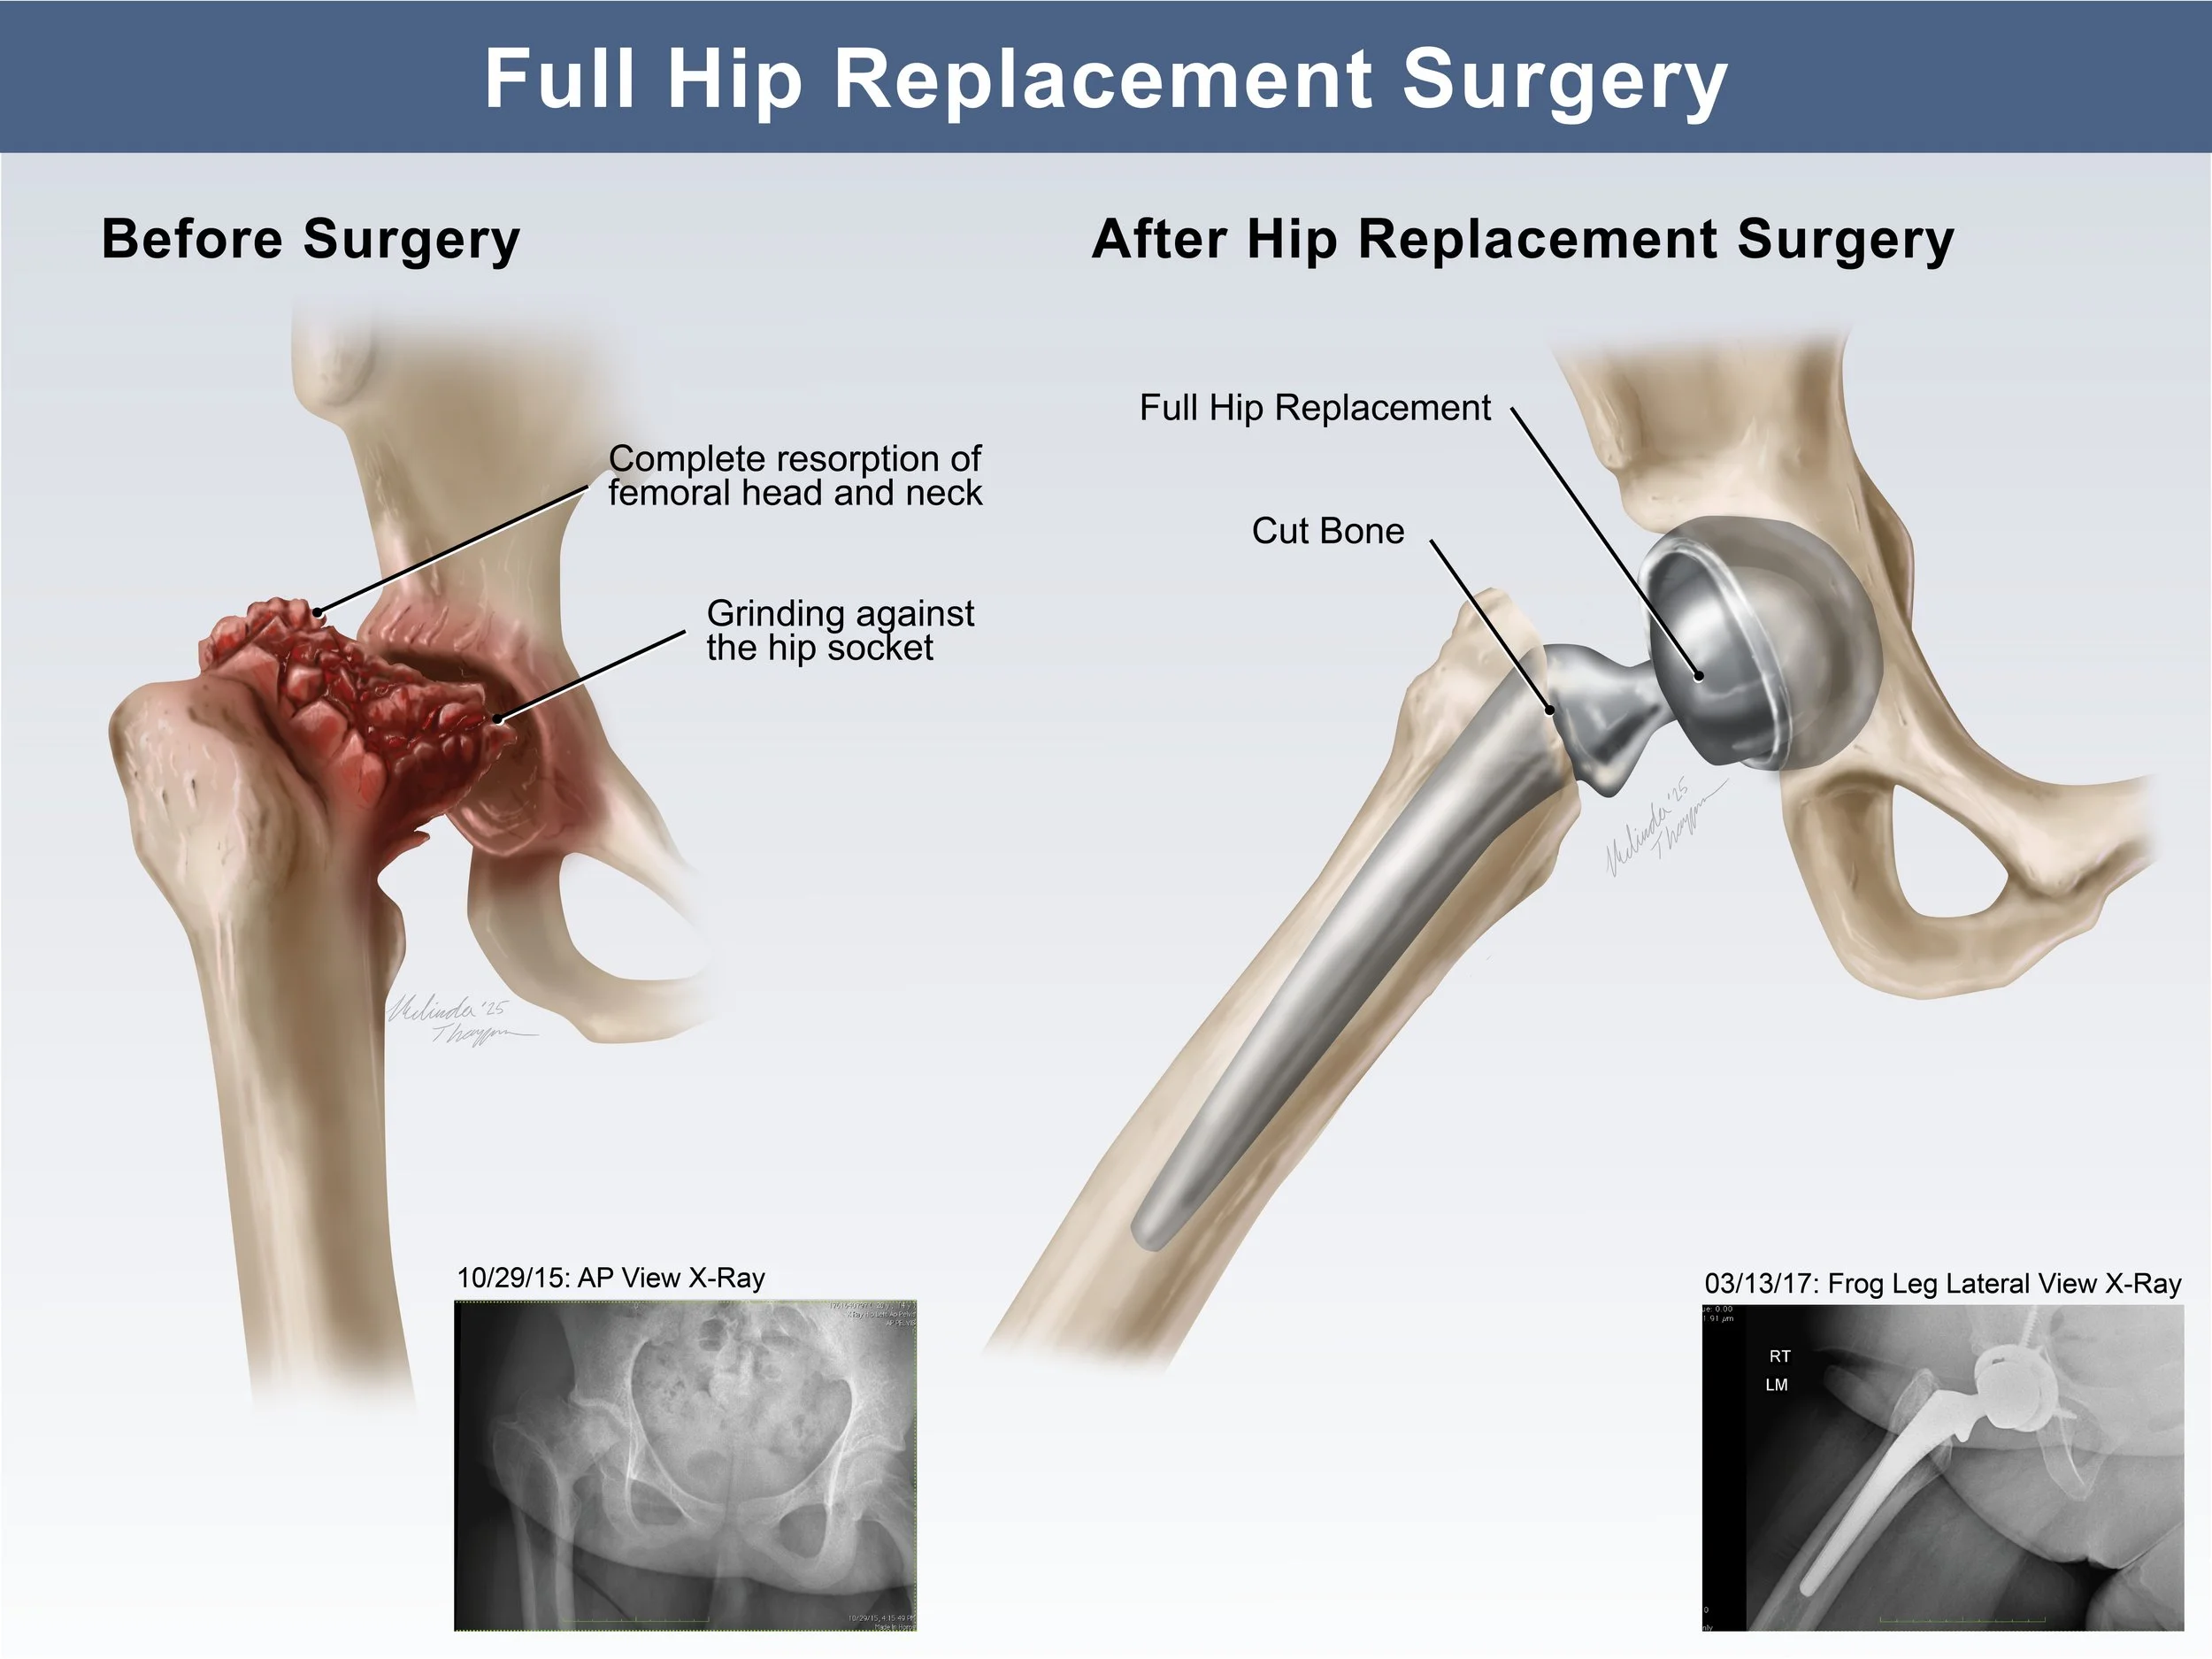

Medical Legal Illustration

Medical Illustration is important in the courtroom for many reasons including communicating scientific information for a lay audience, highlighting injury or anatomical differences, or simply representing potentially disturbing images in a more digestible way. Legal illustrations must be accurate, but still serve to help tell the defendant or plaintiff’s story.

Additional Medical Legal Illustrations